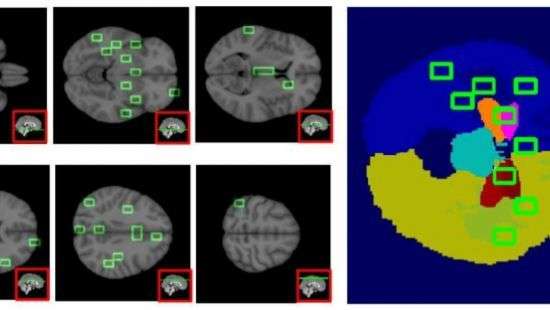

Исследователи из Университета Бари в Италии верят, что проблему может решить искусственный интеллект. Они создали алгоритм машинного обучения, способный выявить вызванные заболеванием крошечные структурные изменения в мозгу за 10 лет до появления симптомов.

Исследователи натренировали искусственный интеллект на основе 67 снимков МРТ (магнитно-резонансной томографии). 38 из них были снимками пациентов с болезнью Альцгеймера, 29 принадлежали здоровым людям. Сотрудники университета разделили снимки на небольшие области и заставили ИИ проанализировать нейронные связи между ними. Они обнаружили, что алгоритм был наиболее точен тогда, когда размер сравниваемых участков мозга равнялся 2250-3200 кубическим миллиметрам. Примерно такой же размер у анатомических структур, связанных с заболеванием — например, у миндалевидного тела и гиппокампа.

После этого они протестировали алгоритм посредством обработки снимков мозга 148 человек. На этот раз 48 снимков относились к пациентам с заболеванием Альцгеймера, ещё 48 — к людям с умеренными когнитивными нарушениями, которые в конечном итоге вылились бы в полноценную болезнь.

ИИ сумел диагностировать болезнь Альцгеймера в 86 % случаев. Что более важно, он смог обнаружить слабые когнитивные нарушения в 84 % случаев, что делает его потенциально полезным для раннего обнаружения заболевания.